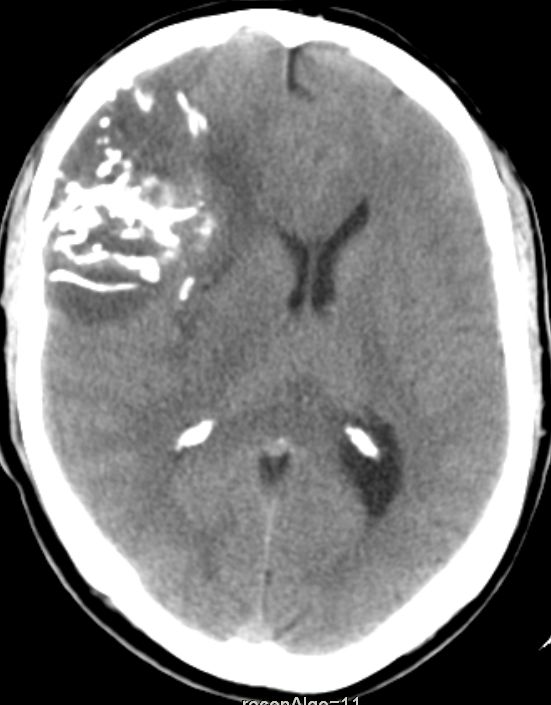

CT

46-jähriger Mann mit anaplastischem Oligodendrogliom WHO-Grad III rechts fronto- parieto-temporal, keine 1p19q-Deletion, IDH-1-Mutation, Ki67 12%.

Der Patient erlitt beim Autofahren einen epileptischen Anfall mit Myoklonien des gesamten Körper und Bewusstlosigkeit.